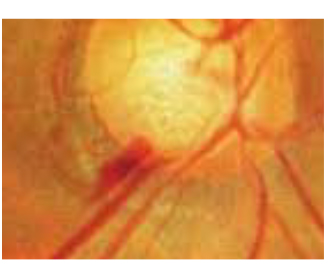

・視神経乳頭陥凹拡大、網膜神経線維束欠損と書いてあったら

上記のように書いてあったら、それは緑内障等眼の神経の病気が隠れている可能性があります。正常の視神経の乳頭部分は若干のへこみがありますが、へこみが大きくなっている場合、脳にいく神経線維の束が痛んでいる事を示唆します。

写真ではこのように写ります。OCTという機器で測定すると網膜の厚みと視神経の状態を解析してくれるので神経が傷んでいる部分が一発で分かります。